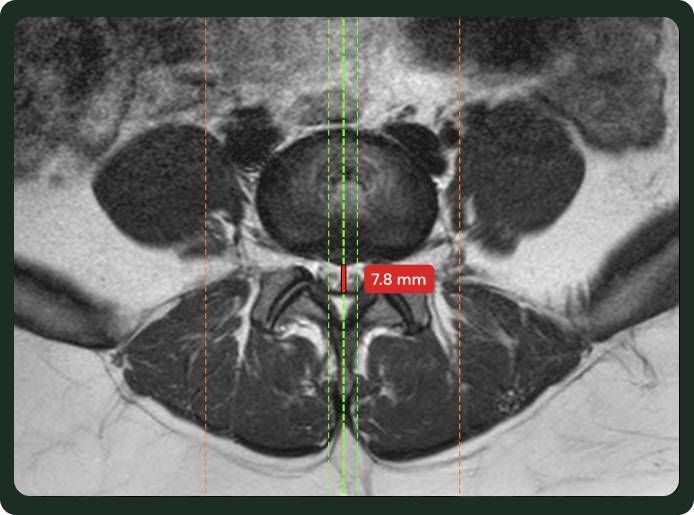

Pfirrmann, disc morphology, stenosis grade, canal narrowing, cord signal, and a red-flag section for cord compression.